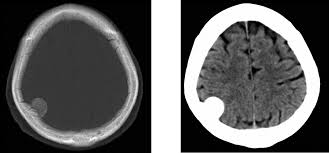

Momento óptimo de la anticoagulación después de un accidente cerebrovascular isquémico con fibrilación auricular: una revisión sistemática

25 junio 2025

En personas con ictus isquémico agudo y fibrilación auricular, el inicio temprano de anticoagulantes orales directos (en los 4 días siguientes al evento) redujo el riesgo del resultado compuesto de ictus isquémico recurrente, hemorragia intracerebral sintomática o ictus no clasificado en los 30 días siguientes. Estos hallazgos respaldan el inicio temprano de ACOD en la práctica clínica.  The Lancet, 23 de junio de 2025.